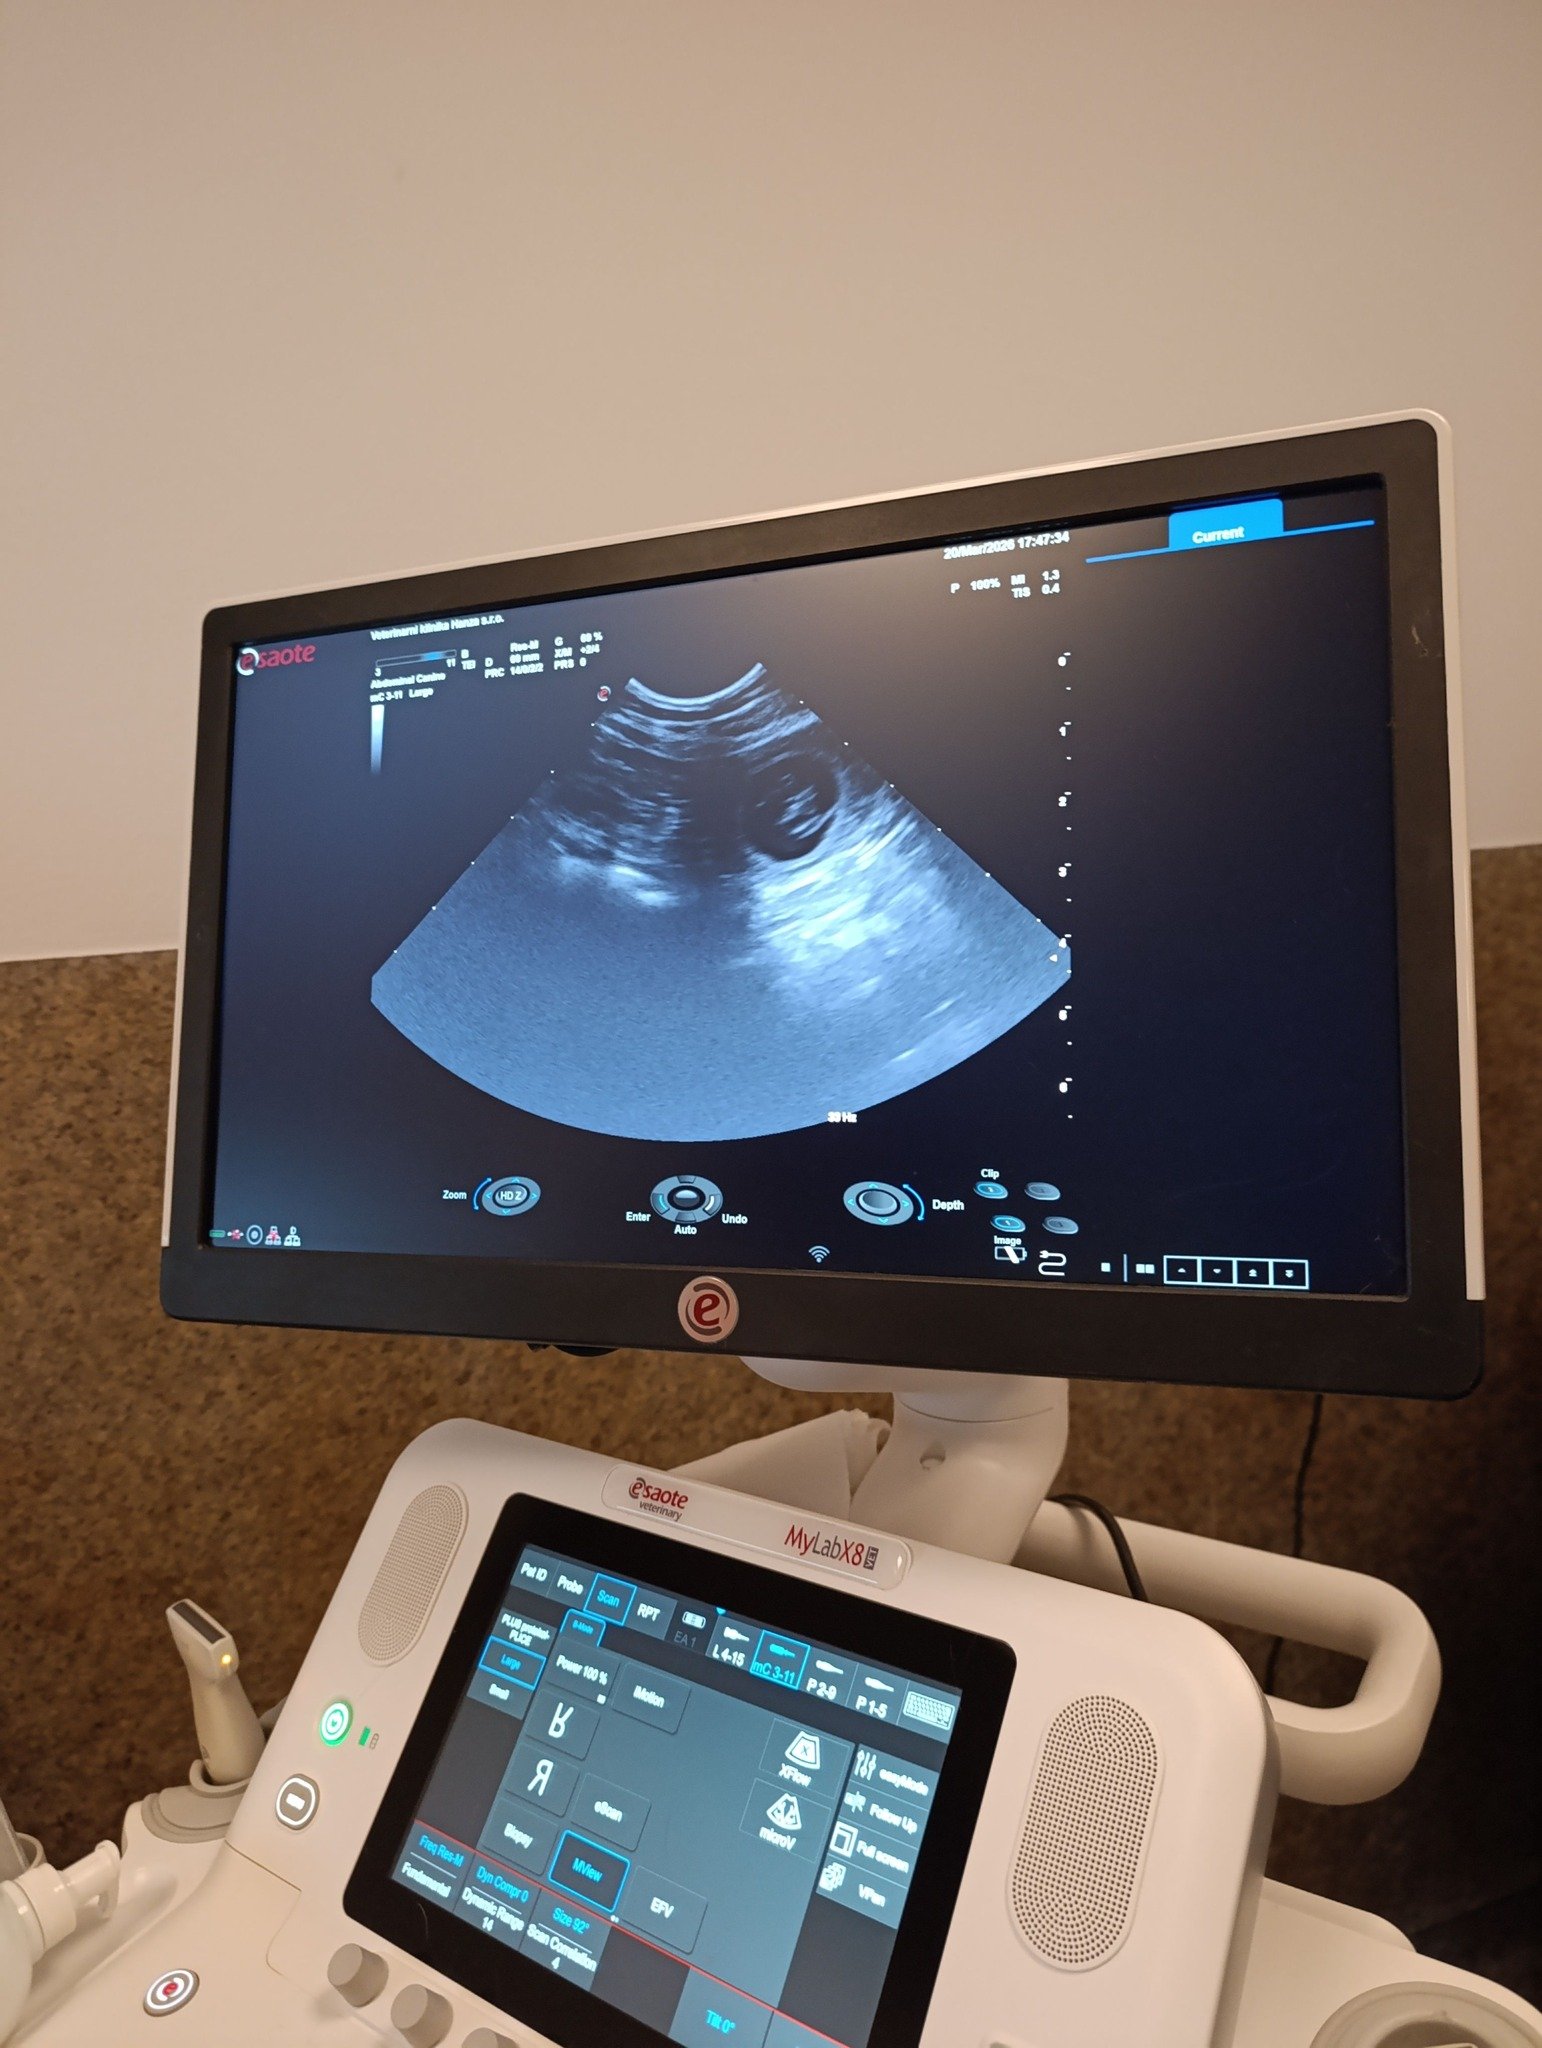

S radostí oznamujeme, že jsme u naší fenečky Bereniky úspěšně potvrdili březost. Proběhlo kontrolní ultrazvukové vyšetření, které potvrdilo, že vše probíhá, jak má, a my se tak můžeme dále těšit na očekávaný vrh.